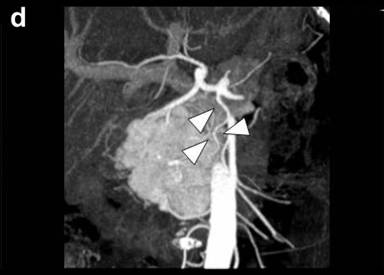

A 67-year-old female was referred to our hospital, complaining of jaundice, appetite loss and 3 kg of body weight loss over one month. She had undergone a thyroidectomy for a thyroid adenoma and a right oophorectomy for an ovarian tumor at 41 years of age and a right nephrectomy for renal cell carcinoma at 47 years of age. Laboratory data demonstrated mild liver dysfunction due to obstructive jaundice without elevation of plasma CEA and CA 19-9 levels. Computed tomography (CT) demonstrated a remarkably enhanced tumor measuring 55x40 mm in diameter in the head, two tumors measuring 2.0 and 1.8 cm in the body, and two tumors measuring 1.2 and 1.0 cm in the tail with a similar enhancing effect (Figure 1abc). CT angiography did not demonstrate any abnormalities of the arteries and the dorsal pancreatic artery branching from the origin of the splenic artery (Figure 1d). Magnetic resonance imaging demonstrated obstruction on the intrapancreatic bile duct due to a pancreatic head tumor and a slight dilatation of the main pancreatic duct in the body and tail of the pancreas. Fluorine-18 fluorodeoxyglucose positron emission tomography detected an elevated uptake in the isolated multifocal metastatic pancreatic tumors without any extrapancreatic uptake. A biliary drainage tube was inserted endoscopically. Cytology of the pancreatic juice was negative. The patient was diagnosed with isolated pancreatic metastases from renal cell carcinoma. The huge tumor located in the head was resected by a pancreaticoduodenectomy and the four tumors located in the body and in the tail of the pancreas were resected by a distal pancreatectomy, preserving the cervical portion. Intraoperative confirmation of arterial perfusion in the middle segment was necessary. In other cases, a total pancreatectomy should be done. Enucleation was not considered due to the risk of main pancreatic duct injury.

Figure 1. Preoperative computed tomography. Pancreatic metastatic tumors were detected as being demarcated enhanced tumors in the tail (a.) and body (b.) of the pancreas. A very large tumor occupied the entire head of the pancreas (c.). The common bile duct was compressed by the tumor located in the head of the pancreas (d.). |

The gastroduodenal artery, splenic artery, and inferior pancreaticoduodenal artery are divided when a middle-preserving pancreatectomy is performed. The dorsal pancreatic artery is the main feeding artery of the remnant middle pancreas. The dorsal pancreatic artery arises most frequently from the initial splenic artery but may also arise from the celiac trunk or common hepatic artery [18]. Whichever vessel the dorsal pancreatic artery originates from, it should run cranial or dorsal to the middle pancreas. Lymph nodes should be carefully dissected. In our patient, ultrasonographic examination was performed after clamping the splenic artery and the tail of the pancreas on the transectional line. Doppler examination showed an arterial flow signal in the middle pancreas.